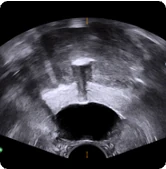

Procedural scan showing placement of the BioProtect Balloon Spacer in a salvage case. Axial view.

Axial Ultrasound

Image courtesy of Dr. Neil Wijetunga, Radiation Oncologist.